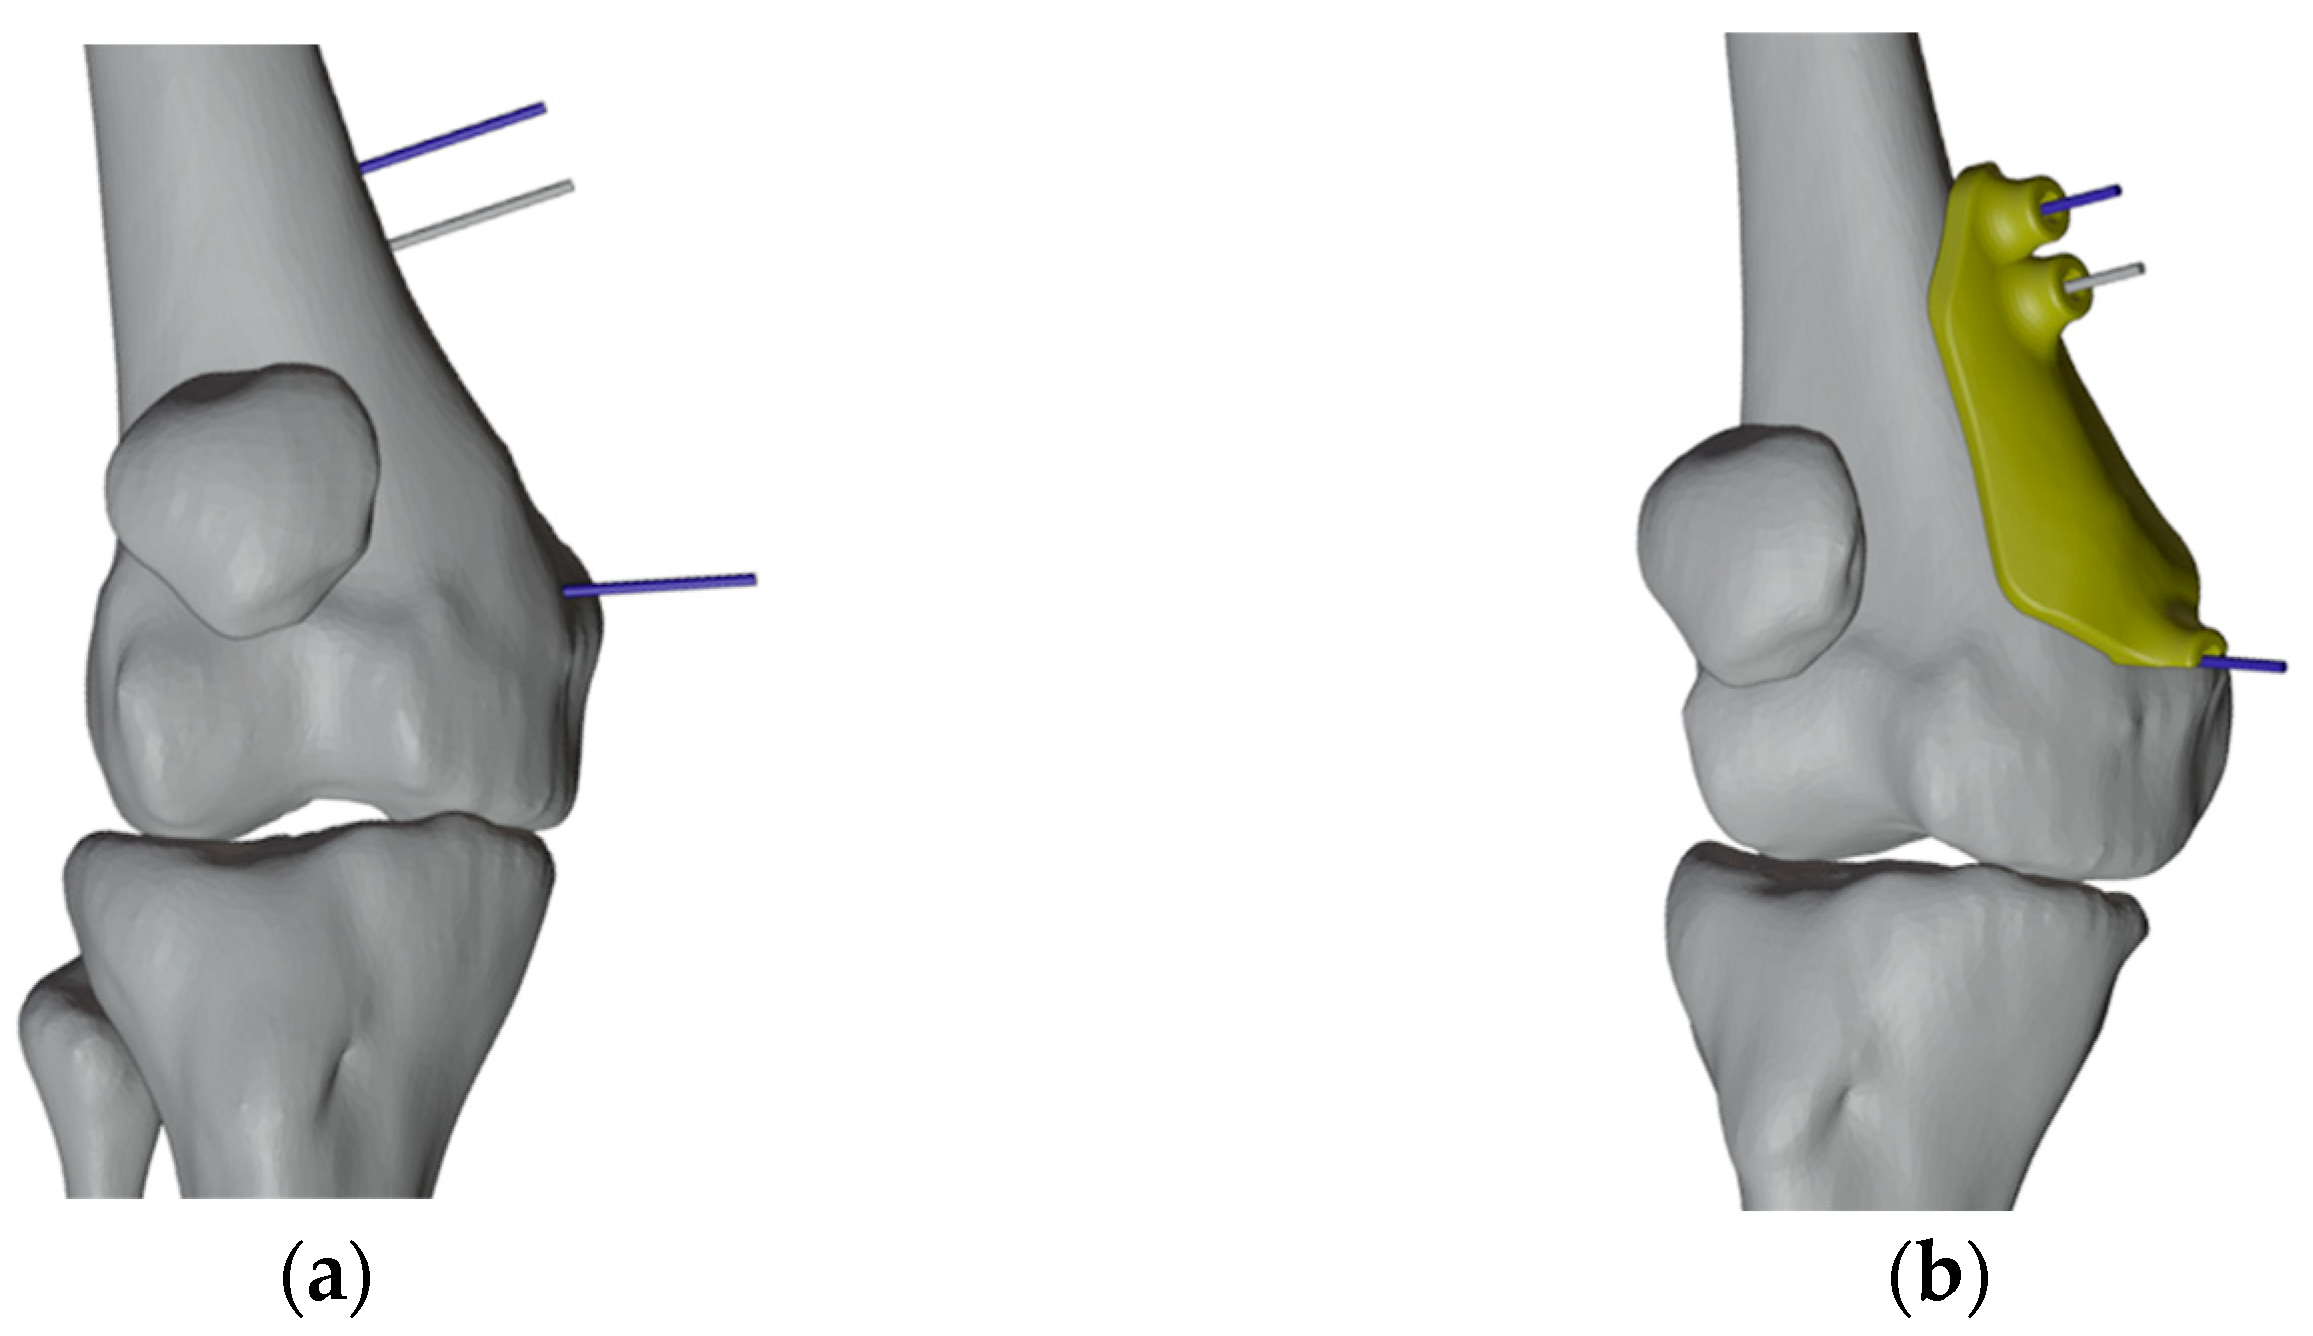

2.4.1. PSIs Design for the Right Femur